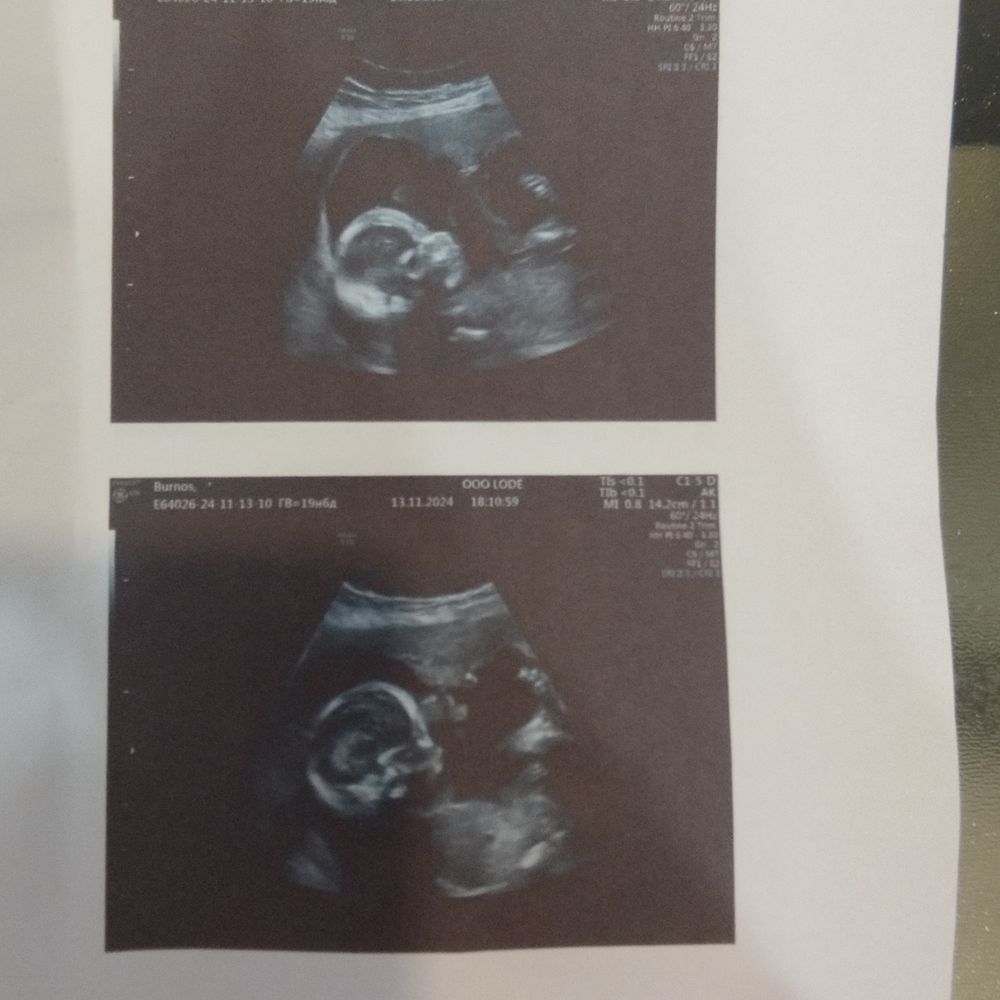

Привет половина беременности

Мальчик

Елена, ну хз хз, такое чувство, то что это торчит - пуповина 🤣🤣🤣 не верю я в то что мой муж после четверых девочек может сделать мальчика 🤣🤣🤣🤣

Пол на первом скрининге Определение Пола по половому бугорку